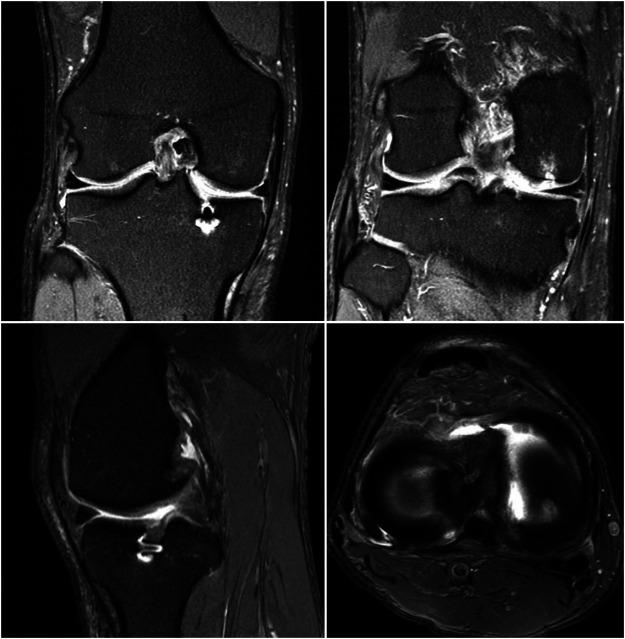

Posterior medial meniscus root tears (PMMRTs) make up a relatively notable proportion of all meniscus pathology and have been definitively linked to the progression of osteoarthritis (OA). While known risk factors for development of OA in the knee include abnormal tibial coronal alignment, obesity and female gender, PMMRTs have emerged in recent years as another significant driver of degenerative disease. These injuries lead to an increase in average contact pressure in the medial compartment, along with increases in peak contact pressure and a decrease in contact area relative to the intact state. Loss of the root attachment impairs the function of the entire meniscus and leads to meniscal extrusion, thus impairing the force-dissipating role of the meniscus. Anatomic meniscus root repairs with a transtibial pullout technique have been shown biomechanically to restore mean and peak contact pressures in the medial compartment. However, nonanatomic root repairs have been reported to be ineffective at restoring joint pressures back to normal. Meniscal extrusion is often a consequence of nonanatomic repair and is correlated with progression of OA. In this study, the authors will describe the biomechanical basis of the natural history of medial meniscal root tears and will support the biomechanical studies with a case series including patients that either underwent non-operative treatment (5 patients) or non-anatomic repair of their medial meniscal root tears (6 patients). Using measurements derived from axial MRI, the authors will detail the distance from native root attachment center of the non-anatomic tunnels and discuss the ongoing symptoms of those patients. Imaging and OA progression among patients who were treated nonoperatively before presentation to the authors will be discussed as well. The case series thus presented will illustrate the natural history of meniscal root tears, the consequences of non-anatomic repair, and the findings of symptomatic meniscal extrusion associated with a non-anatomic repair position of the meniscus.

后内侧半月板根部撕裂(PMMRTs)在所有半月板病变中占比较显著,并且已明确与骨关节炎(OA)的进展相关。虽然已知膝关节OA发展的风险因素包括胫骨冠状面排列异常、肥胖和女性性别,但近年来PMMRTs已成为退行性疾病的另一个重要驱动因素。这些损伤导致内侧间室平均接触压力增加,同时峰值接触压力增加,且相对于完整状态接触面积减小。根部附着的丧失会损害整个半月板的功能,并导致半月板挤出,从而损害半月板的力消散作用。经胫骨拉出技术进行的解剖学半月板根部修复在生物力学上已显示可恢复内侧间室的平均和峰值接触压力。然而,据报道非解剖学根部修复在将关节压力恢复到正常水平方面无效。半月板挤出通常是非解剖学修复的结果,并且与OA的进展相关。在本研究中,作者将描述内侧半月板根部撕裂自然病程的生物力学基础,并将通过一个病例系列来支持生物力学研究,该病例系列包括接受非手术治疗的患者(5例)或内侧半月板根部撕裂接受非解剖学修复的患者(6例)。作者将使用从轴向MRI得出的测量值,详细说明非解剖学隧道与天然根部附着中心的距离,并讨论这些患者的持续症状。还将讨论在向作者就诊之前接受非手术治疗的患者的影像学和OA进展情况。因此呈现的病例系列将说明半月板根部撕裂的自然病程、非解剖学修复的后果以及与半月板非解剖学修复位置相关的有症状半月板挤出的发现。